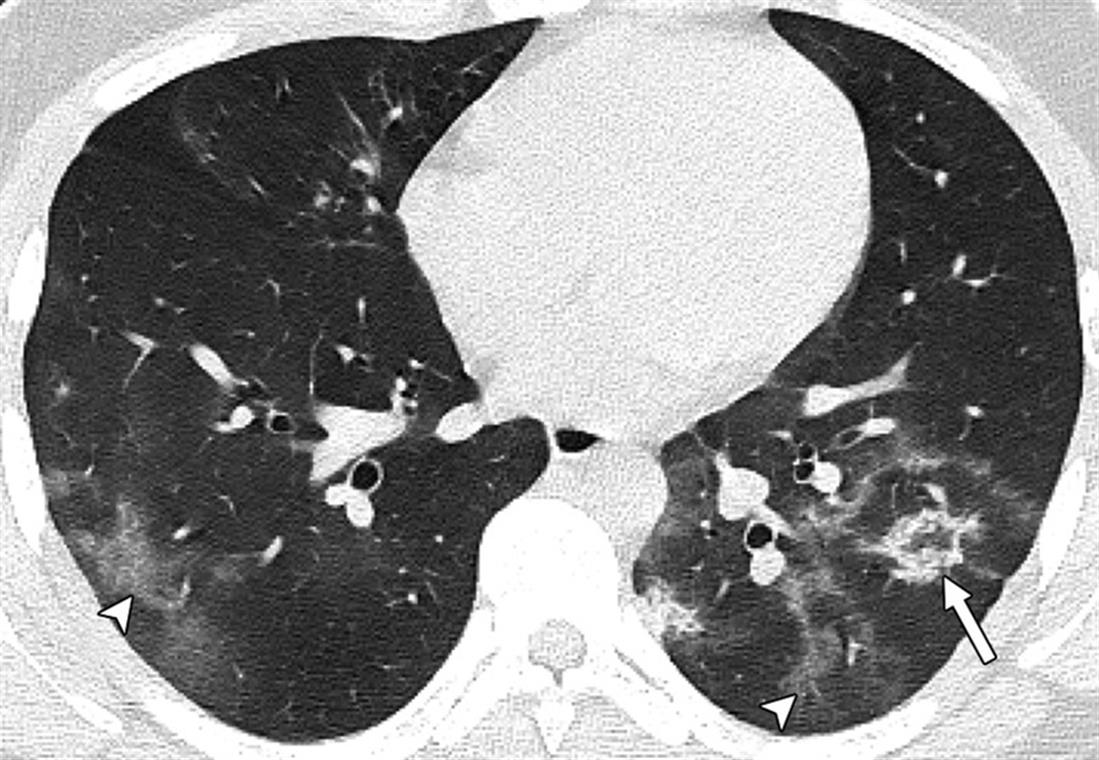

Το μήνυμα συνοδεύεται από αξονικές τομογραφίες νέων, κάτω των 18 ετών, που νόσησαν και δείχνουν τις σοβαρές βλάβες που υπέστησαν στους πνεύμονες.

«Μία εικόνα χίλιες λέξεις.

Αξονικές τομογραφίες νέων κάτω από 18 έτη με COVID-19 (18 ετών, 15 ετών, 14 ετών και 8 ετών). Κανένας ασθενής δεν είχε υποκείμενα νοσήματα ή ανοσοκαταστολή. Οι ασθενείς δεν χρειάστηκαν συμπληρωματικό οξυγόνο, διασωλήνωση ή ΜΕΘ. Πρόκειται για απλά-κοινά περιστατικά COVID-19.

Ωστόσο έχουν πολύ “εντυπωσιακές” βλάβες και είναι άγνωστο τι θα προκαλέσουν αυτές οι βλάβες σε βάθος χρόνου.